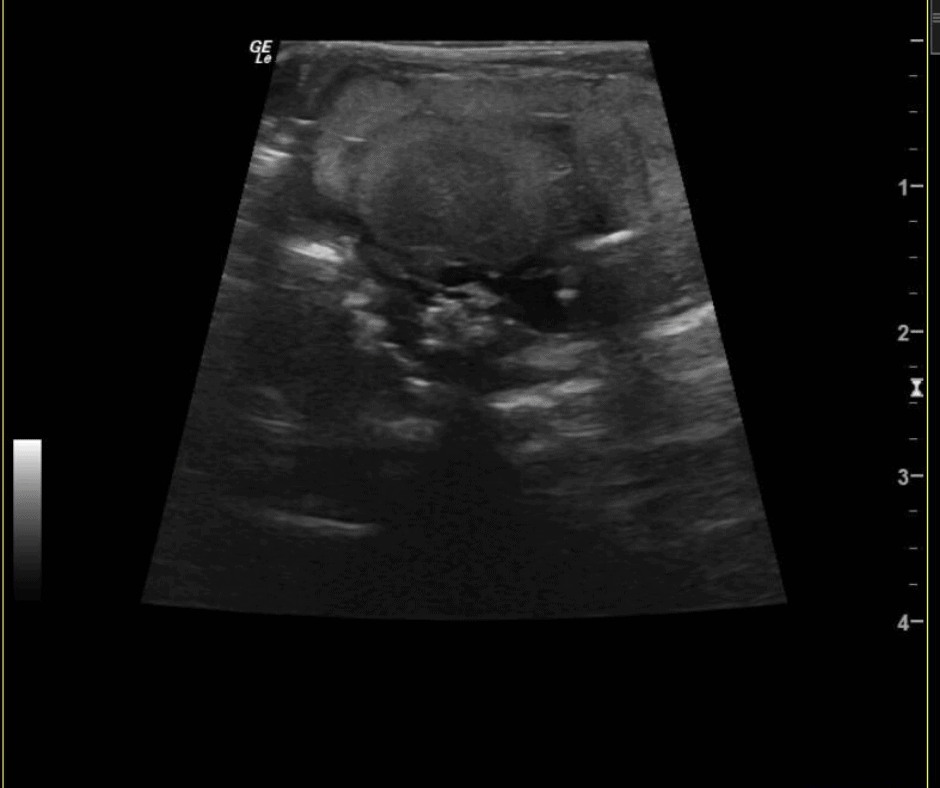

On July 4th we welcomed three tiger rattlesnakes. The gravid (pregnant) female tiger rattlesnake was taken to the Joyce Corrigan Animal Care Center twice for ultrasound exams. The ultra sound images from March 5 show the developing eggs, while the images from March 14 show the snake fetus.